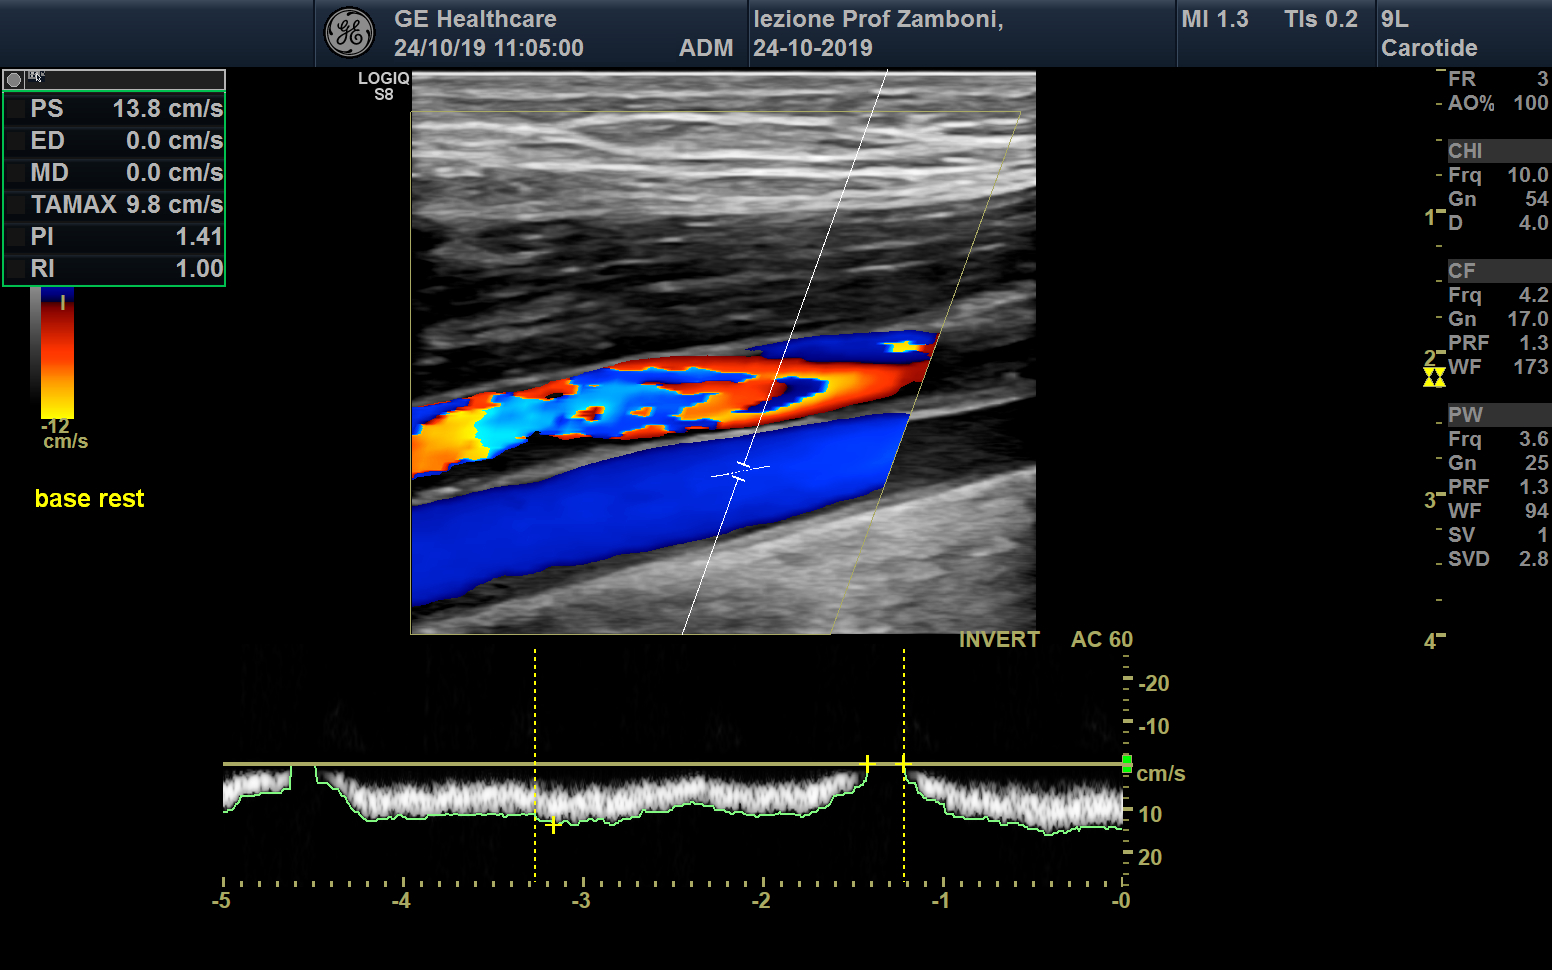

PW V. Femorale base long

JPEG image icon PW V. Femorale base long.jpg — JPEG image, 666 kB (682126 bytes)